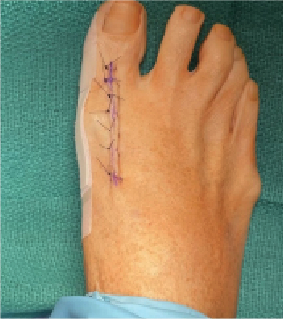

Foot deformity correction procedures often encompass a variety of bone and soft tissue work. After undergoing bunion surgery, the surgeon will likely use splinting as part of the postoperative care to aid healing and maintain the corrected...